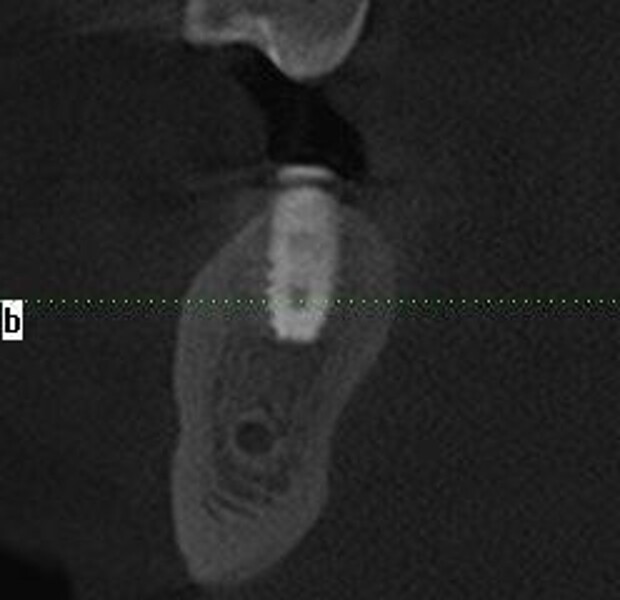

Implantacja z wykorzystaniem szablonu nawigacyjnego 3D